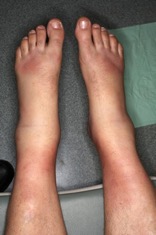

Physical examination. On examination, he was afebrile, and his vital signs were stable. The eyes were normal, and the lungs were clear. There were no murmurs. He had trace edema in both extremities. He had bilateral ankle effusion with soft tissue swelling over both feet. He had erythema nodosum over the ankles and shins (Figure 1). There were no neurologic deficits.

Figure 1. Lower extremities with swollen ankles (arthritis) and erythema nodosum.